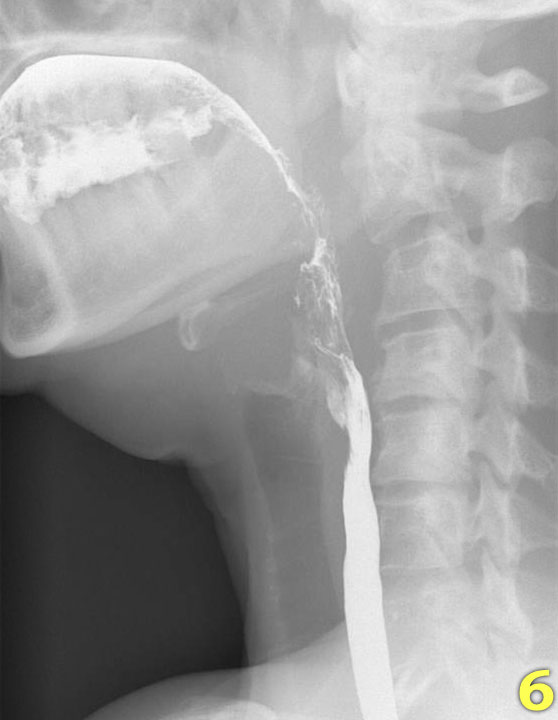

Các hình ảnh quan trọng nhất trong nghiên cứu nuốt là những hình ảnh chụp ở tư thế nghiêng (lateral view).

Nhấp qua các hình ảnh 1-7 ở bên trái.

- Nền lưỡi và vòm miệng mềm đóng khoang miệng ở phía sau (mũi tên) để ngăn thức ăn tràn vào hầu họng và thanh quản đang mở.

- Lưỡi bắt đầu vận chuyển thức ăn về phía hầu họng (mũi tên vàng).

Thanh quản vẫn còn mở và ở vị trí bình thường (mũi tên xanh lá). - Vòm miệng mềm nâng lên để ngăn thức ăn tràn vào vòm mũi họng (mũi tên xanh lá) và lưỡi đẩy thức ăn tiếp tục ra phía sau (mũi tên vàng).

- Xương móng nâng lên và thanh quản đóng lại (mũi tên xanh lá). Lưỡi đẩy thức ăn xuống dưới trong khi cơ khít thực quản trên co lại.

- Sự co thắt của cơ khít hầu giữa (mũi tên vàng), trong khi cơ nhẫn hầu đã giãn hoàn toàn (mũi tên xanh lá).

- Sự co thắt của cơ khít hầu dưới làm tống xuất hầu họng.

- Nắp thanh thiệt nâng lên để trở về vị trí nghỉ và thanh quản mở ra (mũi tên).